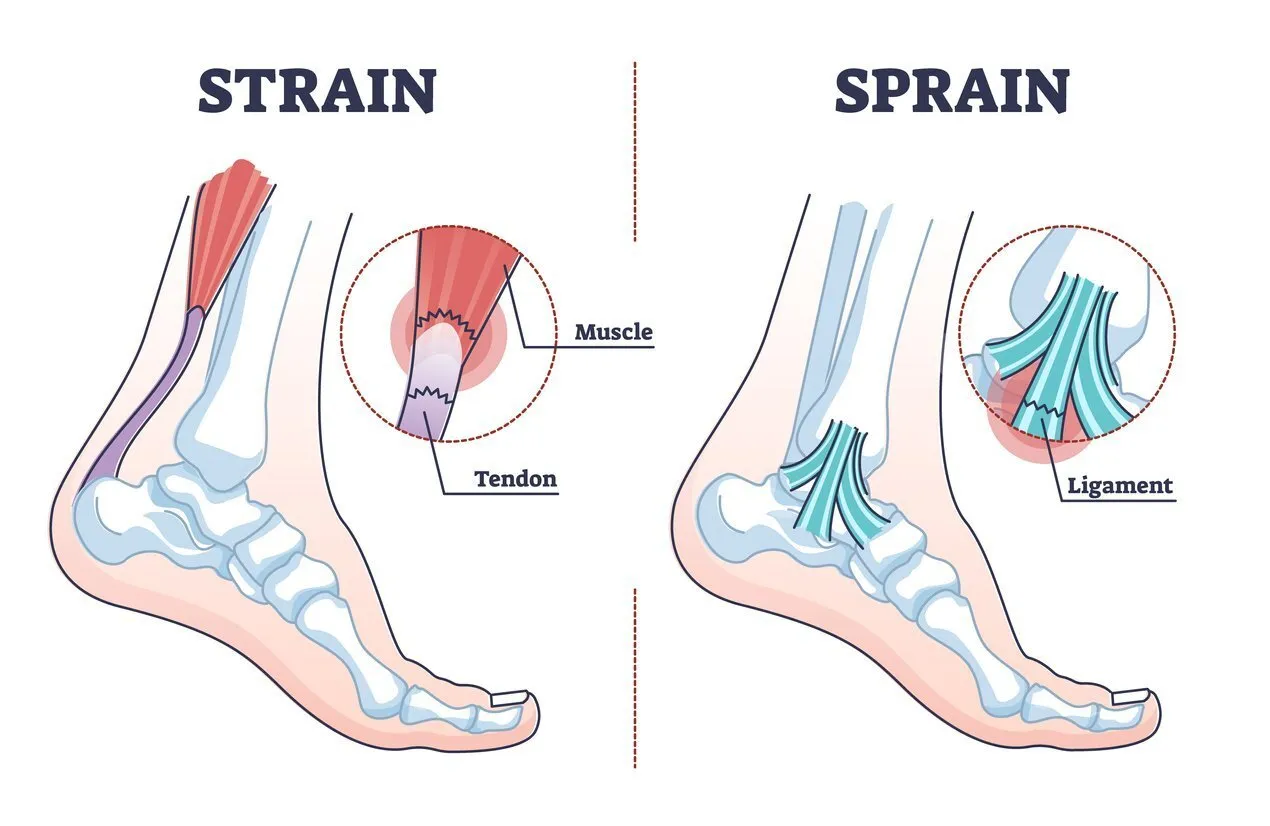

Dr. Harish Talreja is trained to manage traumatic injuries to the bones, joints, and soft tissues, providing timely care to minimize long-term complications.

Whether it’s a torn ACL, rotator cuff injury, or other tendon or ligament issues, Dr. Harish Talreja offers treatment plans tailored to each patient’s needs.